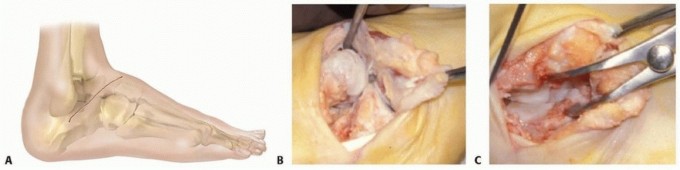

FIGURE 84-14: Coronal section through the metatarsal bases illustrating the Roman arch configuration.

Joint Preparation

The success of any arthrodesis relies on meticulous joint preparation.

1. Exposure: The joint capsules are incised longitudinally and elevated via subperiosteal dissection.

2. Cartilage Removal: All articular cartilage is removed using curettes, osteotomes, and rongeurs. The subchondral bone plate must be completely denuded down to bleeding cancellous bone.

3. Deformity Correction: If a planovalgus or abduction deformity exists, the joint surfaces are contoured using a saw or sharp osteotomes. Plantar-flexion wedges may be removed from the dorsal aspect of the cuneiforms to correct a dorsiflexion (rocker-bottom) deformity.

4. Fenestration: The opposing bony surfaces are fenestrated with a 2.0mm drill bit or a small osteotome to stimulate osteogenesis and vascular ingrowth.